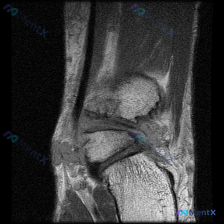

刚看到这份踝关节MRI的读片资料,整理一下病例和完整分析思路,这个病例的鉴别点其实挺典型的,分享给大家。 基本影像信息 这是一张踝关节MRI冠状位T2加权图像,针对影像的观察结果整理如下: 1. 骨性结构:胫骨、腓骨远端及距骨形态基本正常,骨髓信号无明显异常,没有急性骨挫伤、骨髓水肿,也没有明显游离...